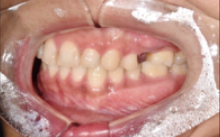

저희 본원에 내 원하신 분으로, 딱딱한 음식을 드시다가 치아가 빠져 내원하신 분이셨습니다.

Before (임플란트 전)

먼저 치아 엑스레이를 촬영하였고, 현재 치아의 상태에 대해 살펴보았습니다.

확인해 보니, 좌측 상단의 치아가 딱딱한 음식을 씹으며 치아가 떨어졌지만, 뿌리가 남아있는 상태로, 발치를 먼저 진행해야 하는 상황이었습니다.